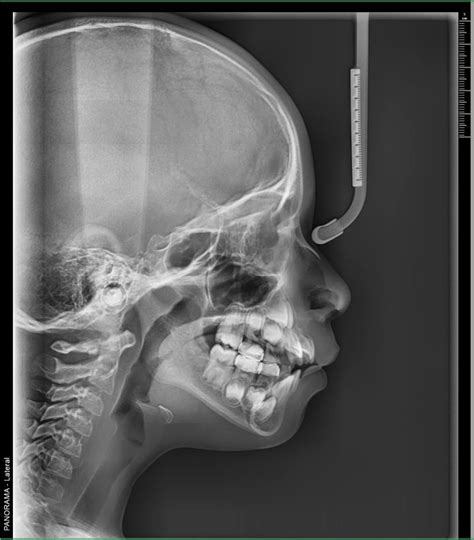

Las radiografías dentales son un tipo de fotografía de los dientes y las estructuras de nuestra boca que se obtienen a través del uso de rayos X. Estas ondas electromagnéticas de alta energía son capaces de atravesar una estructura y formar una imagen. En ellas se muestra la totalidad de la estructura facial y mandibular. Son muy útiles para planificar una ortodoncia.

Las radiografías extraorales son técnicas de diagnóstico por imagen en odontología en las que el sensor o película radiográfica se coloca fuera de la boca del paciente. Es fundamental para los análisis cefalométricos que determinan la posición y alineación de los dientes, así como la relación entre los maxilares y el cráneo.

- Ortopantomografía: También conocida como radiografía dental panorámica, se utiliza para obtener una visión general de toda la cavidad bucal con el fin de detectar anomalías como inflamaciones radiculares, tumores y abscesos o ver la posición de las muelas del juicio que aún no han erupcionado. A diferencia de las radiografías intraorales, la película o el sensor se encuentra fuera de la zona bucal.